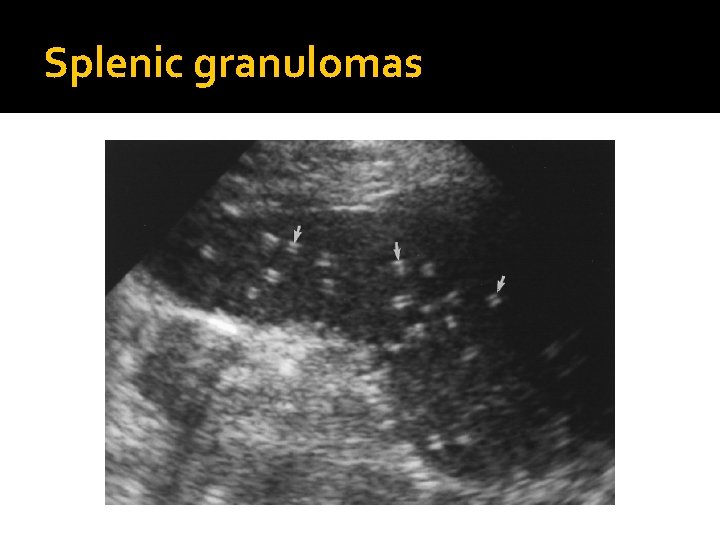

Splenic Calcifications �Granulomas are focal lesions resulting from previous infections. They are seen as focal bright echogenic lesions, with or without shadowing. �Histoplasmosis and tuberculosis are the most common causes of granulomas. �Granulomas are also found in the liver and lungs. �Other splenic calcifications can be associated with Splenic artery or splenic artery aneurysms Splenic infarct (as they evolve)

Splenic granulomas